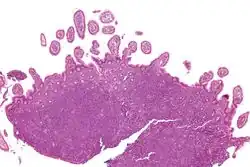

Micrograph showing mantle cell lymphoma (bottom of image) in a biopsy of the terminal ileum. H&E stain.

Micrograph of terminal ileum with mantle cell lymphoma (bottom of image). H&E stain.